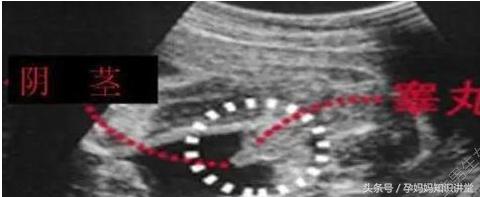

B超单看胎儿性器官

普通来说假如怀的是男孩,那麼B超上有三个点+小鸡鸡。